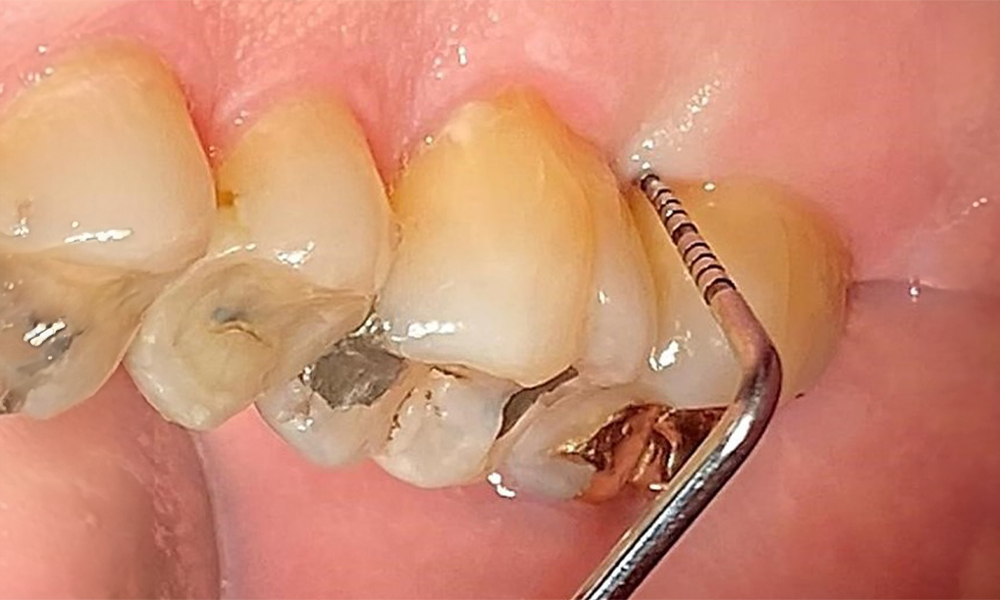

There are no limitations regarding the choice of instrumentation methods. Regular supragingival and subgingival instrumentation is essential to prevent disease progression due to the pre-existing periodontitis and high risk of recurrence. There are no limitations placed on the selection of instruments for mechanical biofilm removal from a general medical perspective, and removal should be performed as needed. Hard and mineralized plaque, such as calculus and concretions, should be removed using manual instruments or sonic/ultrasonic scalers (Fig. 9) (8, 9).

Use an ultrasonic tip to remove hard, mineralized plaque (Proxeo Ultra scaler with the Perio tip, W&H, shown here).

Fig. 9: Use an ultrasonic tip to remove hard, mineralized plaque (Proxeo Ultra scaler with the Perio tip, W&H, shown here). © Dr R. Krapf